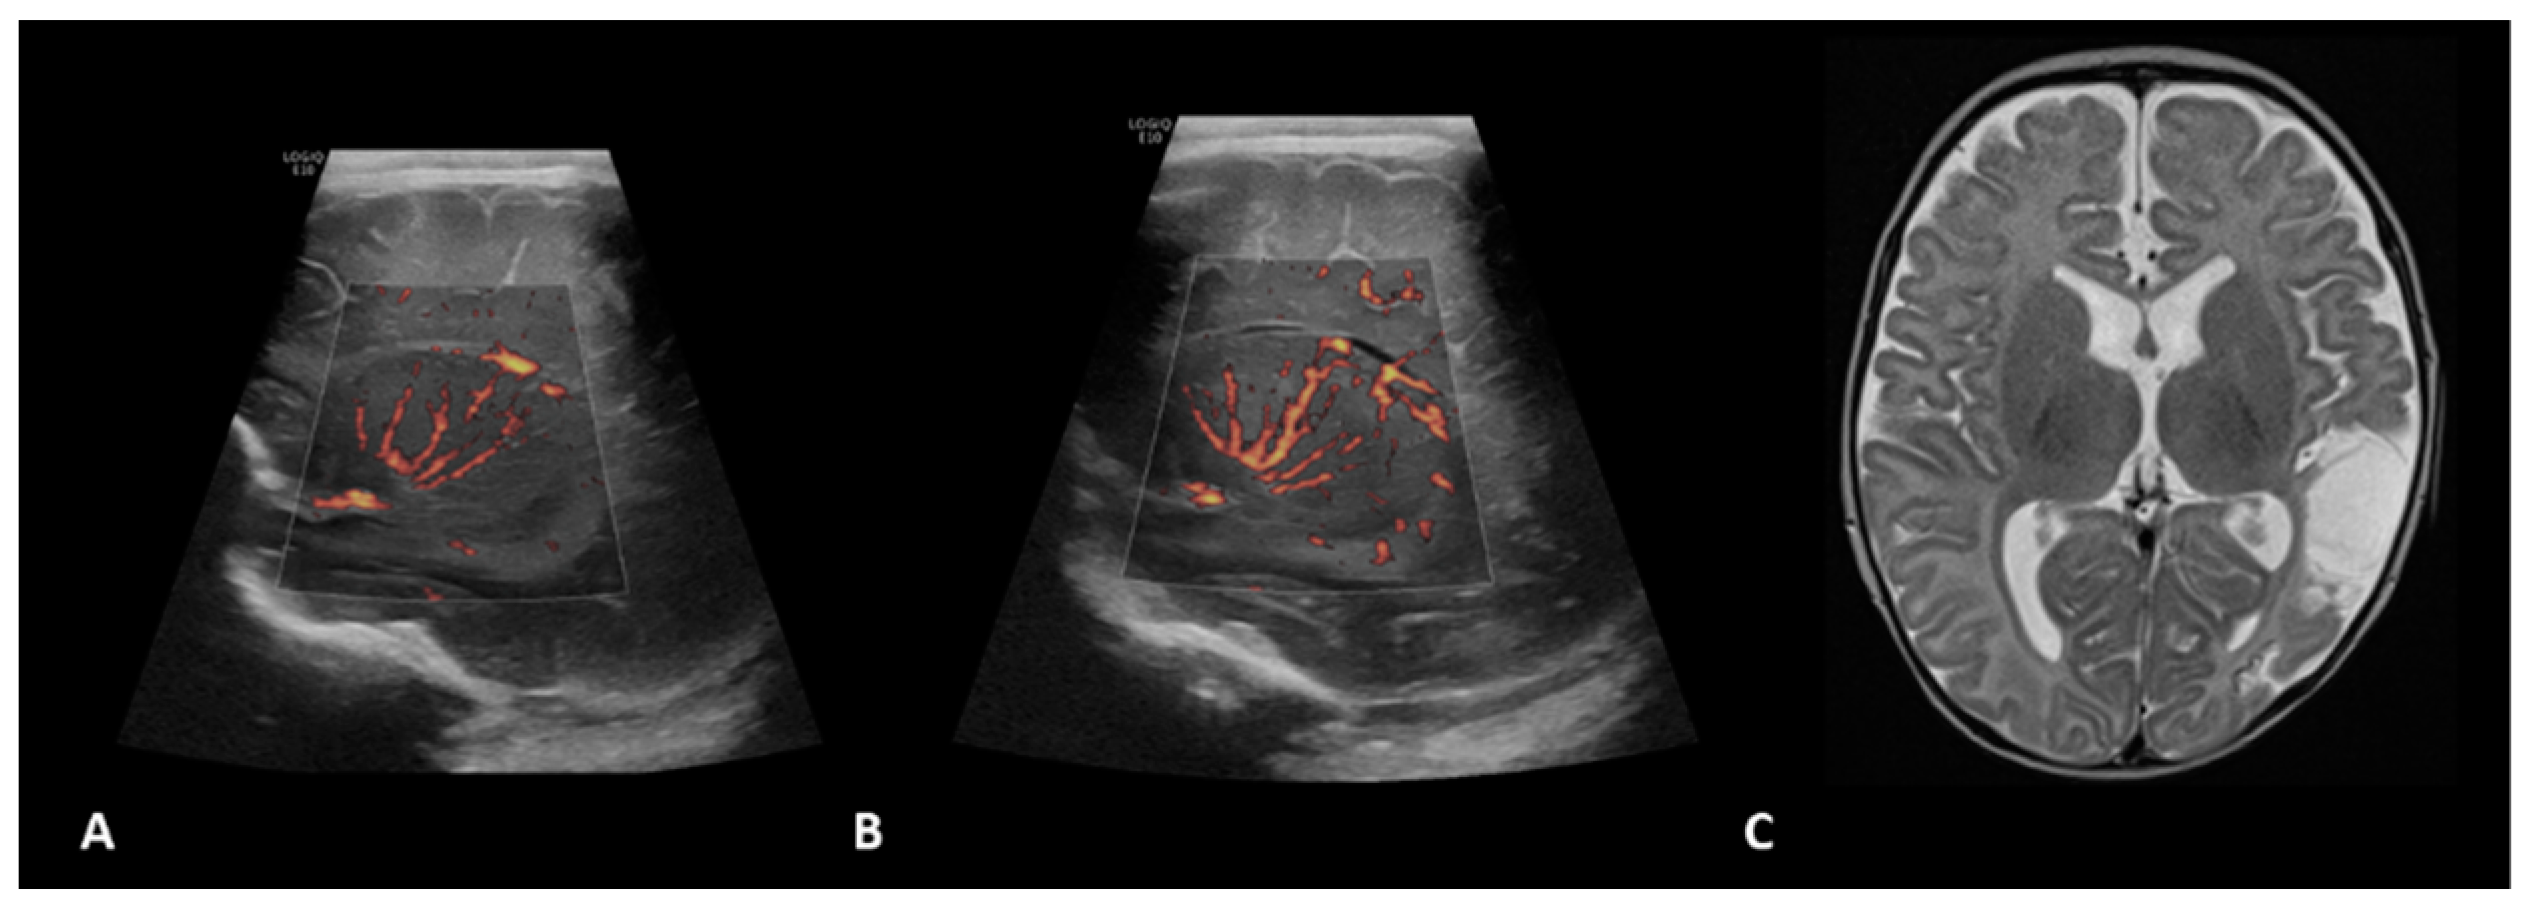

- Hwang, M.; Haddad, S.; Tierradentro-Garcia, L.O.; Alves, C.A.; Taylor, G.A.; Darge, K. Current understanding and future potential applications of cerebral microvascular imaging in infants. Br. J. Radiol. 2022, 95, 20211051. [Google Scholar] [CrossRef] [PubMed]

- Barletta, A.; Balbi, M.; Surace, A.; Caroli, A.; Radaelli, S.; Musto, F.; Saruggia, M.; Mangili, G.; Gerevini, S.; Sironi, S. Cerebral superb microvascular imaging in preterm neonates: In vivo evaluation of thalamic, striatal, and extrastriatal angioarchitecture. Neuroradiology 2021, 63, 1103–1112. [Google Scholar] [CrossRef]

- Goeral, K.; Hojreh, A.; Kasprian, G.; Klebermass-Schrehof, K.; Weber, M.; Mitter, C.; Berger, A.; Prayer, D.; Brugger, P.C.; Vergesslich-Rothschild, K.; et al. Microvessel ultrasound of neonatal brain parenchyma: Feasibility, reproducibility, and normal imaging features by superb microvascular imaging (SMI). Eur. Radiol. 2019, 29, 2127–2136. [Google Scholar] [CrossRef] [PubMed]